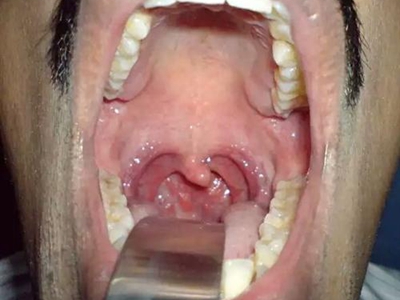

慢性咽炎患者可出现咽部异物感、痒感、干燥感等。常有黏稠分泌物附着于咽后壁,使患者晨起时出现咳嗽伴恶心。慢性单纯性咽炎检查可见黏膜充血,血管扩张,咽后壁有散在淋巴滤泡,常有少量黏稠分泌物附着在黏膜表面。